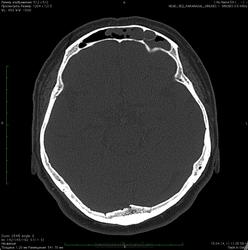

Женщина 58 лет.

Пришла на КТ от ЛОР-врача с диагнозом "хронический фронтальный синусит".

Очень любопытно Ваше мнение -  чем вызвана локальная деструкция задней стенки пазухи?

Субтотальное однородное затенение левой лобной пазухи и " чистые"остальные околоносовые пазухи не исключают объемный процесс от слизистой, в т.ч. с  локальной деструкцией задней стенки, дифференцировать с мукоцеле.

мукоцеле + "атрофия от давления"- может быть, но и гнойный фронтит с деструкцией задней стенки  нельзя не учитывать.

По нативной КТ - в головном мозге все спокойно.

кстати деструкция здесь не только задней стенки, но и нижней - кистозное образование (а их тут я насчитал 2) распространяется в решетчатую кость, занимая часть ее ячеек.

Посмотрел исследование в Дайком формате, полистал в МРR, нет деструкции задней стенки лобной пазухи. Как и предполагал, для вывода о деструкции   из контекста всего исследования взяты единичные срезы. Да и при наличии деструкции задней стенки уже проявились бы  грозные осложнения:  воспалительный процесс распространяется на переднюю черепную ямку, вызывая одно или сразу несколько внутричерепных осложнений: экстра- или субдуральпый абсцесс. гнойный менингит или менингоэнцефалит, абсцесс головного мозга или тромбоз верхнего сагиттального или пещеристого синуса.

я дефект вижу. вот он, даже на реконструкции прекрасно виден.

дефекта нижней стенки вы тоже не видите? ячейки решетчатой кости на Ваш взгляд в полном порядке?